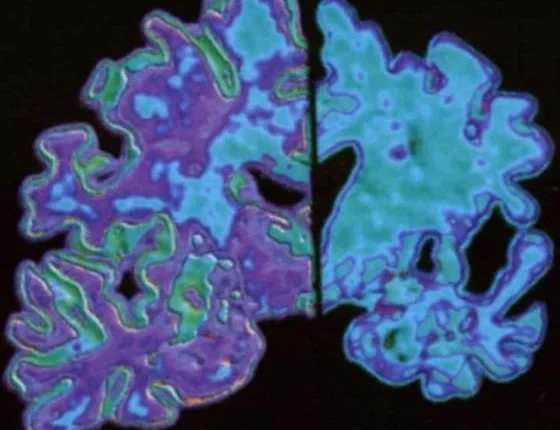

Περίπου 250.000 Αυστραλοί υποφέρουν σήμερα από άνοια και με δεδομένη τη γήρανση του πληθυσμού, αυτός ο αριθμός αναμένεται να αυξηθεί στο ένα εκατομμύριο μέχρι το 2050. Οι ερευνητές προσδιόρισαν βιολογικούς δείκτες που βασίζονται στο αίμα και οι οποίοι σχετίζονται με τη συσσώρευση του β-αμυλοειδούς, μιας τοξικής πρωτεΐνης στον εγκέφαλο, η οποία εμφανίζεται χρόνια προτού εμφανιστούν τα συμπτώματα και προτού έχει συμβεί η μη αναστρέψιμη βλάβη του εγκεφάλου.

«Μια άλλη πρόσφατη μελέτη από την ομάδα AIBL έδειξε ότι τα επίπεδα β-αμυλοειδούς γίνονται ανώμαλα 17 χρόνια περίπου πριν εμφανιστούν τα συμπτώματα άνοιας», είπε η Δρ Burnham. «Αυτό μάς δίνει πολύ περισσότερο χρόνο για να παρέμβουμε και να προσπαθήσουμε να επιβραδύνουμε την εξέλιξη της νόσου».